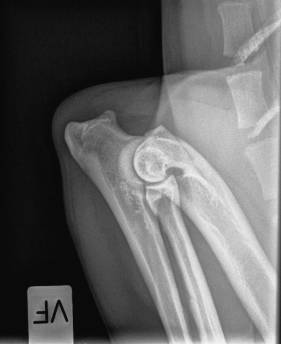

AD Højre 0

AD Venstre 0

AD: 0/0